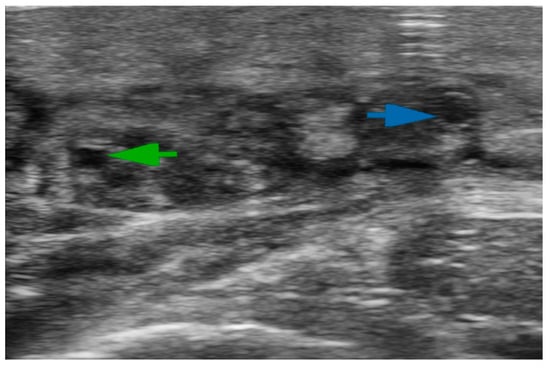

- Mihara, M.; Hara, H.; Kawakami, Y. Ultrasonography for Classifying Lymphatic Sclerosis Types and Deciding Optimal Sites for Lymphatic-Venous Anastomosis in Patients with Lymphoedema. J. Plast. Reconstr. Aesthetic Surg. 2018, 71, 1274–1281. [Google Scholar] [CrossRef]

- Bianchi, A.; Visconti, G.; Hayashi, A.; Santoro, A.; Longo, V.; Salgarello, M. Ultra-High Frequency Ultrasound Imaging of Lymphatic Channels Correlates with Their Histological Features: A Step Forward in Lymphatic Surgery. J. Plast. Reconstr. Aesthetic Surg. 2020, 73, 1622–1629. [Google Scholar] [CrossRef]

- Hayashi, A.; Yamamoto, T.; Yoshimatsu, H.; Hayashi, N.; Furuya, M.; Harima, M.; Narushima, M.; Koshima, I. Ultrasound Visualization of the Lymphatic Vessels in the Lower Leg. Microsurgery 2016, 36, 397–401. [Google Scholar] [CrossRef]

- Hayashi, A.; Hayashi, N.; Yoshimatsu, H.; Yamamoto, T. Effective and Efficient Lymphaticovenular Anastomosis Using Preoperative Ultrasound Detection Technique of Lymphatic Vessels in Lower Extremity Lymphedema. J. Surg. Oncol. 2018, 117, 290–298. [Google Scholar] [CrossRef]